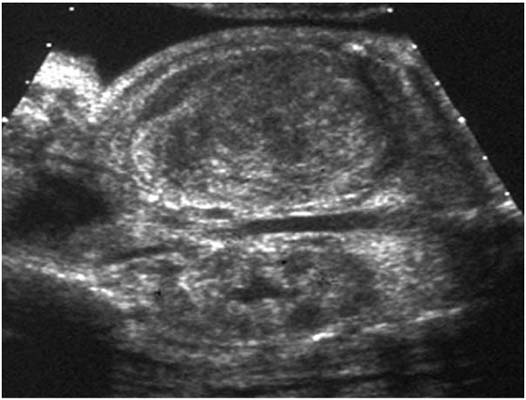

Tumeur de Bolande